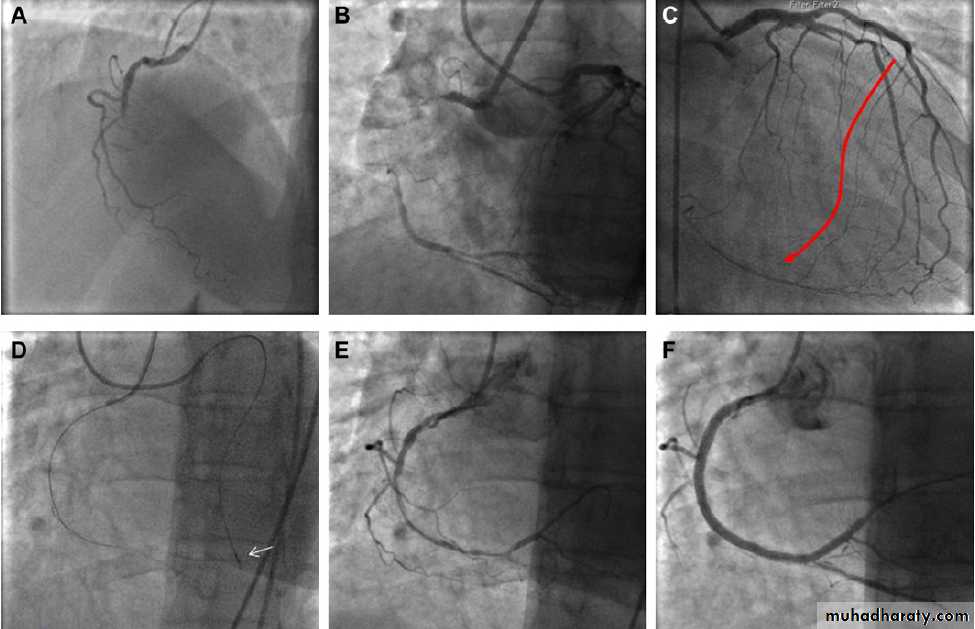

Figure 1 Example of a chronic total occlusion (CTO) of the right coronary artery (RCA) that was treated successfully through a retrograde approach.

The patient was a 56-year-old woman with single vessel disease and class II angina despite good medical treatment. The occlusion had previously

been attempted (unsuccessfully) from an antegrade approach. (A) Baseline image. (B) The length of the occlusion can be estimated from simultaneous

injections into both the left and right coronary arteries.

(C) A septal collateral vessel can be seen supplying blood to the distal RCA. This has several

promising features in that it is of relatively large calibre for such a vessel, has a relatively straight course, and joins the distal vessel without severe

angulation. (D) The collateral was wired with a Fielder FC wire supported by a Corsair catheter (arrow). (E) Using the retrograde wire as a guide, the

antegrade wire was able to be manipulated into the same channel as the retrograde wire and delivered into the distal RCA. The vessel was pre-dilated

in the usual manner and then stented. (F) Final result.